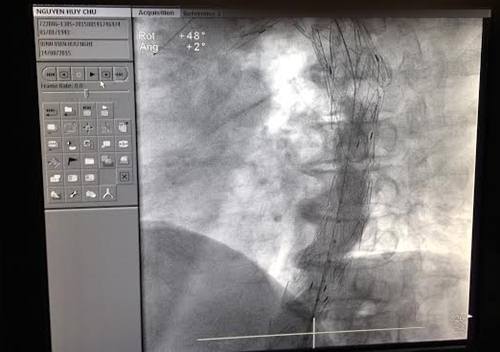

Hình ảnh chụp sau can thiệp đặt stent graft của bệnh nhân Nguyễn Huy Ch. |

Thủ thuật can thiệp đặt stent graft động mạch chủ ngực - bụng đã được thực hiện cấp cứu vào tối ngày 14/8 tại khoa tim mạch can thiệp Bệnh viện Hữu Nghị. Sau 2 giờ làm việc hết sức khó khăn và căng thẳng của các bác sỹ, ca thủ thuật đã thành công, nguy cơ vỡ các ổ phình đã được ngăn chặn”.